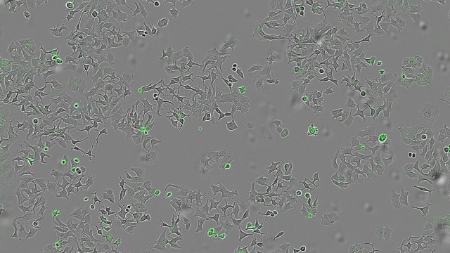

تیم پژوهشی با انجام آزمایشهایی روی گونههای جهشیافتهٔ وبا که فاقد این پروتئین بودند همچنین روی نوع دیگری از باکتری که بهصورت ژنتیکی طوری تغییر یافته بود که فقط HapA تولید کند، نشان داد که تنها در حضور HapA، زندهمانی سلولهای توموری کاهش مییابد.

آنها همچنین بررسی کردند که آیا HapA در برابر انواع مختلف غدههای سرطانی مؤثر است یا نه، و برای این کار مایعی حاوی تمام پروتئینهای ترشحشده توسط باکتری را روی ردههای سلولی سرطان پستان، روده و پانکراس اعمال کردند.

هورتادو گفت: «ما میخواستیم ببینیم آیا سلولهای انسانی از انواع مختلف غده سرطانی، پس از تماس با این مواد باکتریایی، بهویژه با پروتئین HapA، باز هم زنده میمانند و میتوانند تکثیر شوند یا نه.»